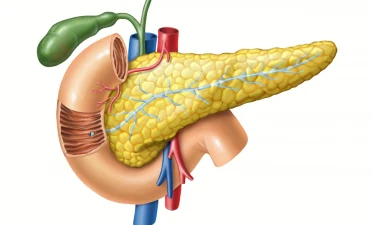

Biopsia de pancreas reprezintă o metodă exploratorie cu rol diagnostic ce presupune prelevarea unei probe de țesut de la nivel pancreatic, cu scopul identificării naturii unor leziuni, precum și a gradului lor de evoluție și severitate.